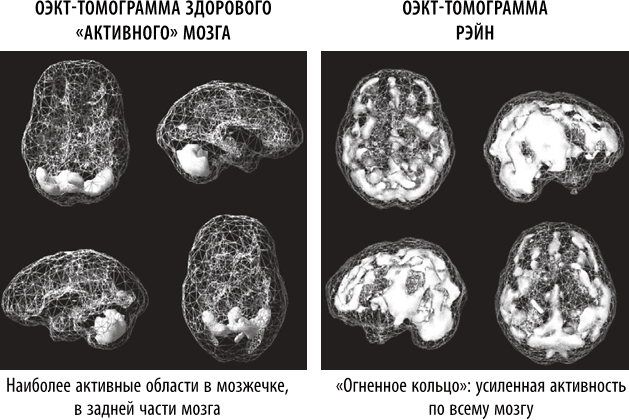

ОЭКТ-томограмма Рэйн выявила сильную аномалию. У нее был так называемый «паттерн огненного кольца», который характеризуется чрезмерной активностью всего мозга, особенно в области передней поясной извилины. Это означало, что она зацикливается на негативных мыслях и поступках. Было легко называть ее плохой девочкой, пока мы не увидели, в каком состоянии находился ее мозг. Мозг ребенка был постоянно перенапряжен, оставляя ей слишком мало возможностей для контроля над своим поведением. Мы назначили Рэйн специальные добавки, чтобы успокоить ее мозг, организовали ей посещение нейротерапевта и изменили ее рацион, исключив глютен и молочные продукты.